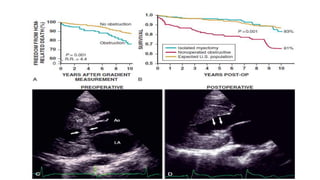

Natural history

Risk of Sudden Death

(LVEF >35%)

Maggioni AP. GISSI-2 Trial Circulation. 1993;87:312-322.

EF<35%

(LVEF < 35%)

NO PVC

SOME PVC

MANY VPCo PVBs

1-10 PVBs/h

> 10 PVBs/h

0.86

A

0.88

0.90

0.92

0.94

0.96

0.98

1.00

0 30 60 90 120 150 180

Days

Survival p log-rank 0.002

Survival

B

p log-rank

0.0001